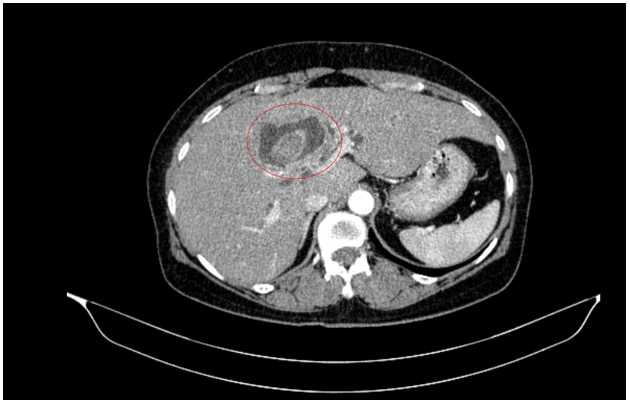

Chụp cắt lớp vi tính bụng - tiểu khung: Hình ảnh giãn đường mật trong gan phải/Sonde dẫn lưu đường mật gan phải - Gan trái đã cắt.

Hình 7. Phim chụp cắt lớp vi tính vụng cho thấy phần gan trái đã cắt (hình mũi tên)- Sonde dẫn lưu đường mật gan phải( vòng tròn đỏ).